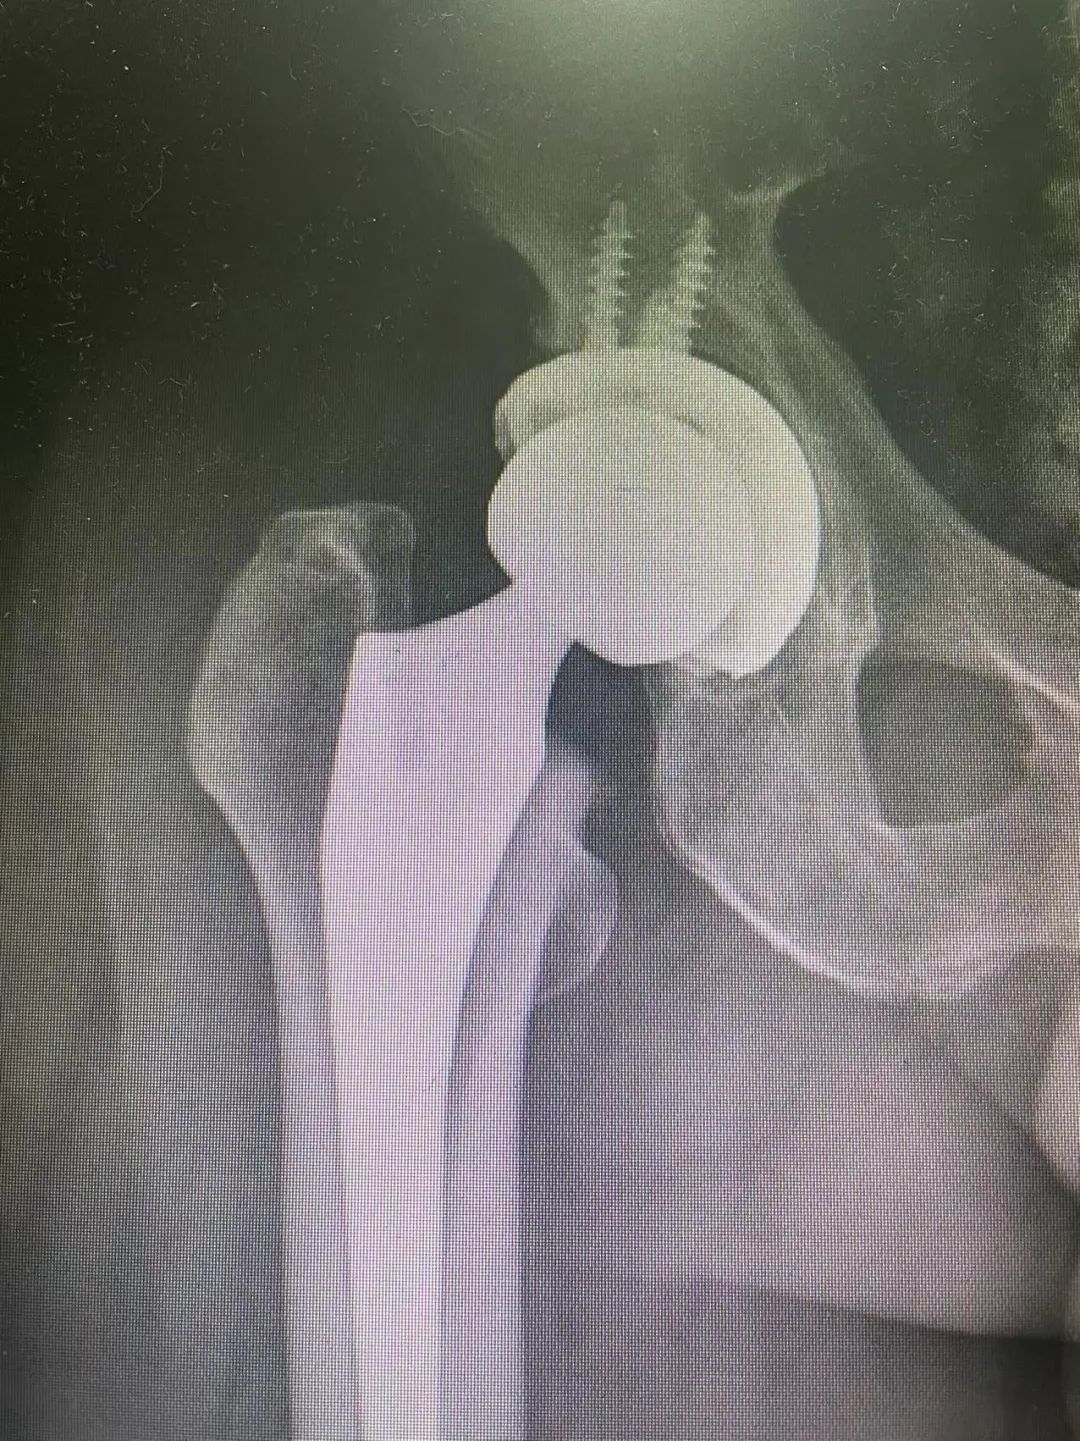

下图为CT测量前倾角(图8)

Nho(1)等人比较了六种放射检查方法(Lewinnek,Widmer,Hassan,Ackland,Liaw,以及Woo and Morrey)与CT测量的准确性,报告称使用Widmer和Ackland方法获得的测量值与CT测量值有显著差异,而其他方法则没有。

他们的结论是,Lewinnek、Hassan、Liaw以及Woo and Morrey的方法是准确的。Marx(2)等人比较了五种平片方法(Pradhan、Mclaren、Hassan、Ackland、Widmer)与CT测量的准确性,并得出结论,Widmer的方法比其他方法的误差率更小。T. Nomura(3)在研究中发现Widmer的方法在分析前倾角时存在一些小错误。考虑到x线平片成本低、放射水平低、随访方便、髋臼假体位置评估方便等优点,误差在临床可接受范围内。研究表明Widmer的方法是评估x线平片前倾的最佳方法。

考虑到x线平片的成本低、放射水平低、随访和髋臼假体位置评估方便等优点,可以考虑用Widmer的方法是评估x线平片前倾。但X片测量髋臼假体的前倾角没有CT准确,存在着一定的误差。出于科学或临床的原因,如果需要准确的数值,CT检查可能是必要的